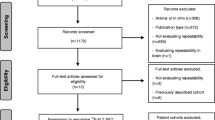

Overall, 14 patients were recruited (mean age, 67 years +/− 12, 8 men). They had 22 tumours between them, comprising 12 primary lung cancers, 8 metastatic lymph nodes in the thorax and 2 distant metastases within the field of view. Details of the patients, their demographics and their lesions are presented in Table 1. All patients had either completed induction chemotherapy or were not eligible for chemotherapy, except for patient 4 who underwent concurrent chemoradiotherapy. Therefore, changes in MRI biomarkers were considered largely due to radiation. Sample images are shown in Fig. 1.

Histograms revealed skewed, distributions of all MRI biomarker parameters that deviated from normality except for pre-treatment median IAUC60 and pre-treatment median ve (Fig. 2A, B and Supplementary Table S1). Bland-Altman plots in test-retest baseline MRI biomarker data (Fig. 2C) showed that measurement error was only constant over the range of biomarker values for median IAUC60. Consequently, all biomarkers underwent a logarithmic transformation.

Histogram distributions of the cohort parameter values for each of the six MRI biomarkers at (A) pre-treatment baseline and (B) week 2 of treatment. Measurement error of the test-retest replicates pre-treatment is shown in C with Bland-Altman plots, where the top and bottom dotted lines indicate LOA